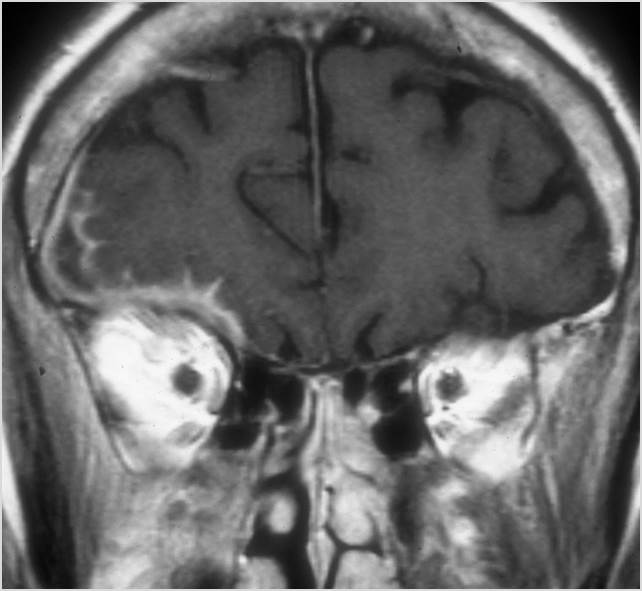

Intracranial

There is evidence of thrombus, thrombophlebitis or other occlusive or inflammatory process of the cavernous sinus. [Yes/No]

There is brain abscess specifically involving the frontal and temporal lobes. [Yes/No]